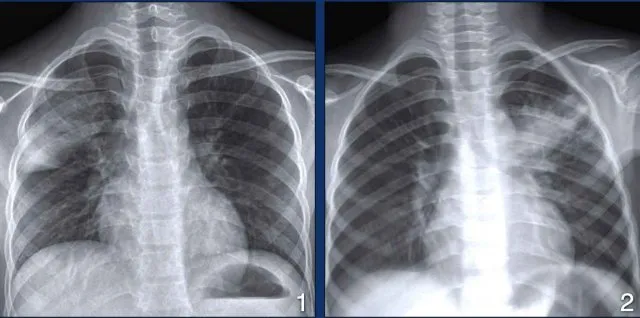

- Key Dx: Sputum smear (ZN), Culture (LJ - Gold Std), CBNAAT (rapid, Rif-R), CXR (cavities, Ghon complex), TST.

- Tuberculosis: Ghon complex (primary TB), DOTS strategy, BCG vaccine for prevention.